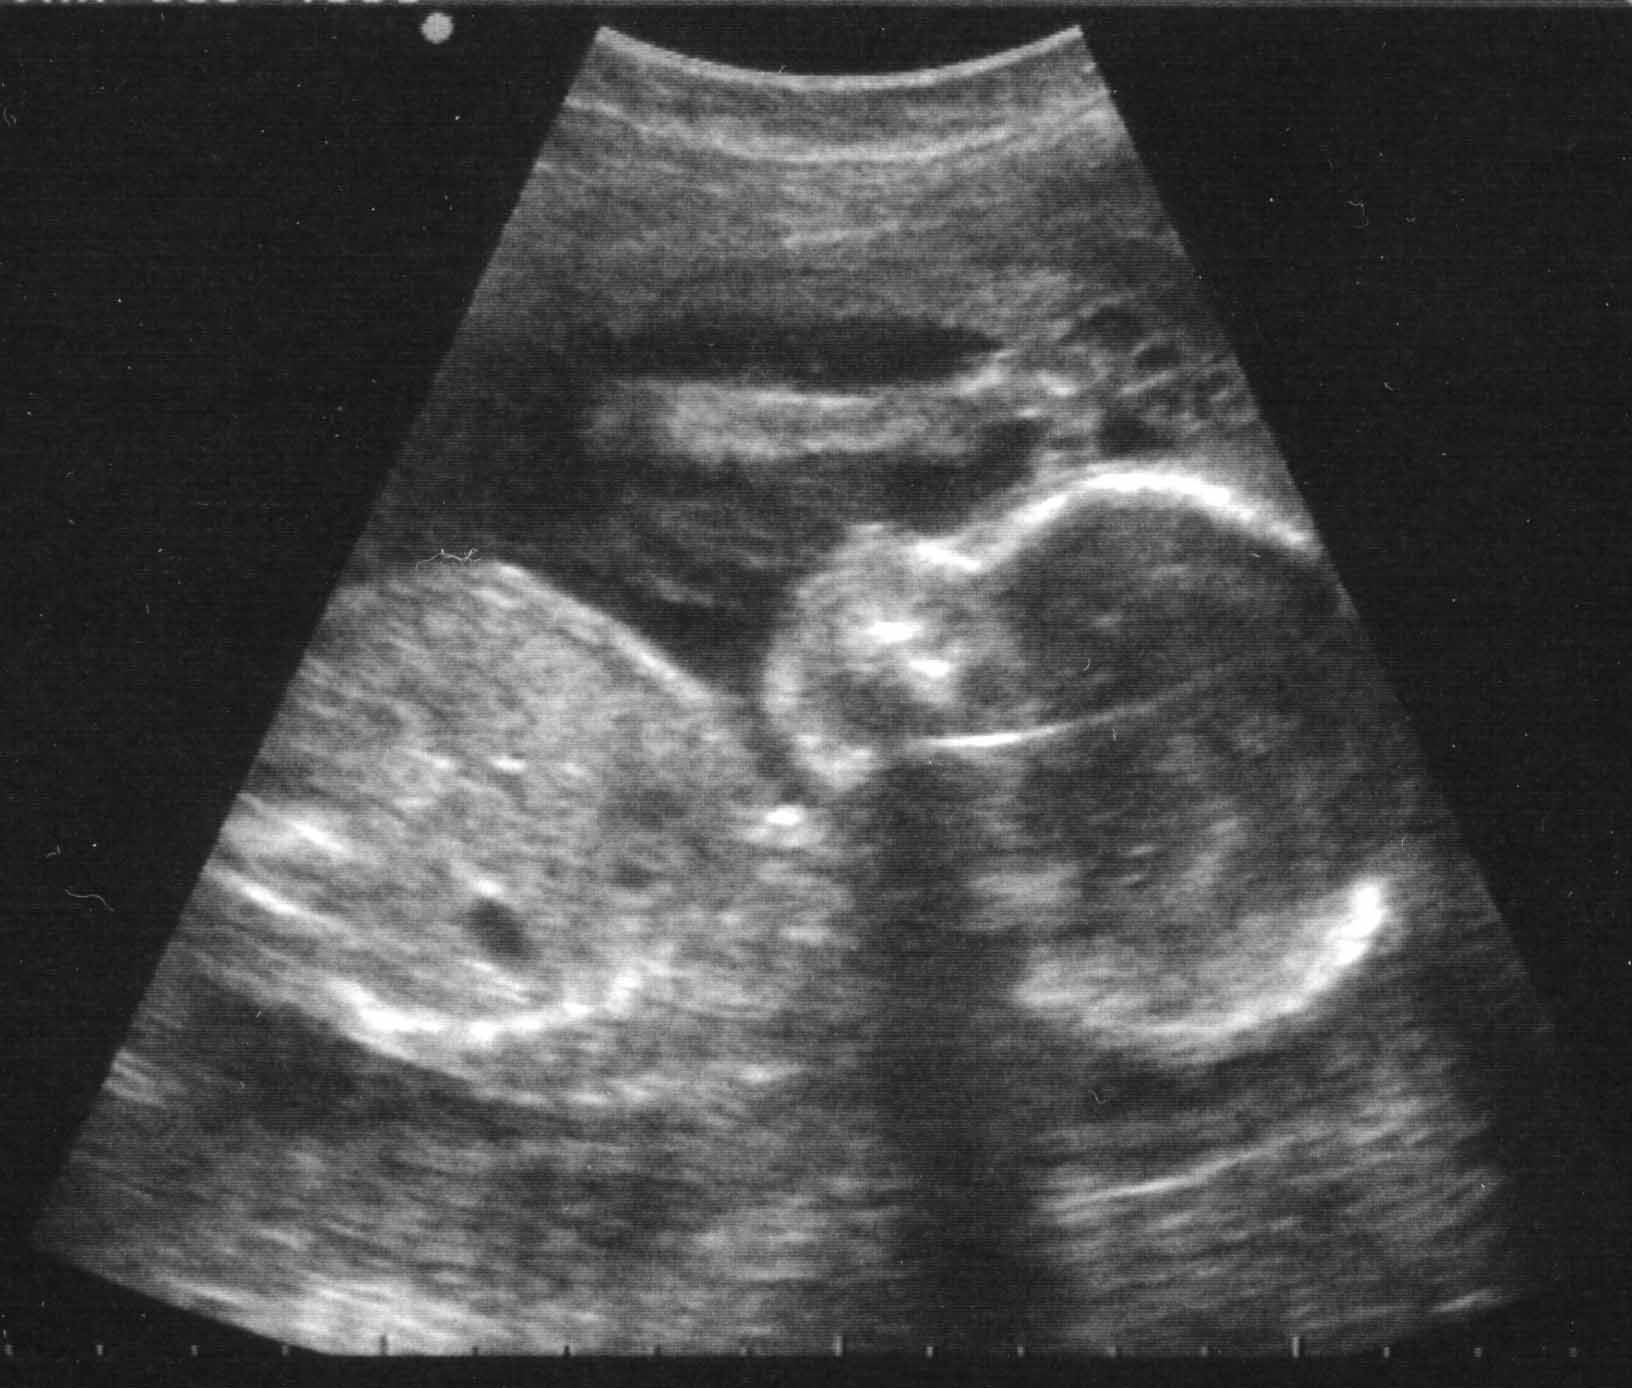

Another taxonomic scheme for ultrasound visualization is based on the different types of data the technique utilized. 3D Freehand and 4D ultrasound, pose very different challenges compared to 2D ultrasound or when handling multiple modalities. Blending b-mode ultrasound for tissue and color-doppler ultrasound for blood flow can be challenging enough in 2D if not in 3D. An example image is shown in Figure 1d. In addition to the ultrasound input, the combination of other medical imaging modalities, such as CT or MRI with ultrasound, provide more information, but also more challenges to the visualization researcher.

Different anatomic regions have different characteristics in ultrasound images, as can be seen in Figure 1. For instance, in a liver scan one might look for tumors using a high-resolution abdominal 2D probe. For heart infarctions, the doctor might need to examine the strain in the heart muscle to detect defect muscle tissue. The wide spread in tissue and pathology difference lead to anatomically specific visualization techniques.

Figure 1: Example ultrasound images from the cardiac (a), gastric (b), fetal (c) and Blood flow (d) domain.